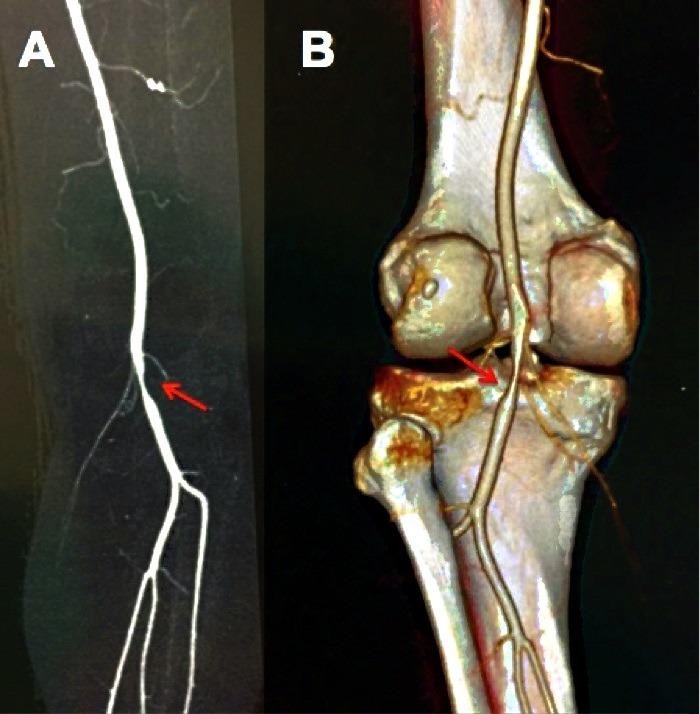

Adventitial cystic disease of the popliteal artery is an uncommon pathology that should be considered in differential diagnostic of younger patients with intermittent claudication and without risk factors for peripheral atherosclerotic arterial disease. We report the case of a 51 year-old male patient presenting with lower-limb intermittent claudication in whom this pathology was diagnosed and who was treated with segmental arterial resection and autologous saphenous vein interposition. We also discuss diagnostic and therapeutic alternatives.

腘动脉外膜囊肿性疾病是一种罕见的病理学情况,在诊断较年轻的间歇性跛行且无外周动脉粥样硬化性疾病危险因素的患者时应予以考虑。我们报告一例51岁男性患者,其因下肢间歇性跛行就诊,被诊断为此种疾病,并接受了节段性动脉切除及自体大隐静脉移植术治疗。我们还讨论了诊断和治疗的其他选择。